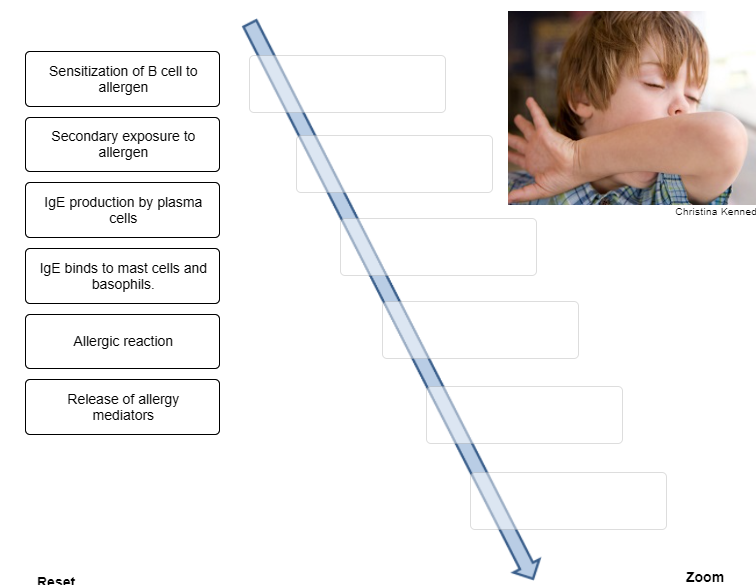

Put the steps that occur during an immediate-reaction allergic response in the correct order.

Place the steps that occur during an immediate-reaction allergic response in the correct order.

1. Indicate the order of cell types involved in the response to the

first exposure to an allergen.

2. Antibodies attach to mast cells

via what part of the antibody structure?

3. With second exposure

to an antigen, the antigen molecules bind to __________.

1. Antigen-presenting cell, helper T cell, B cell, plasma

cell

2. Constant region

3. IgE on the mast cells